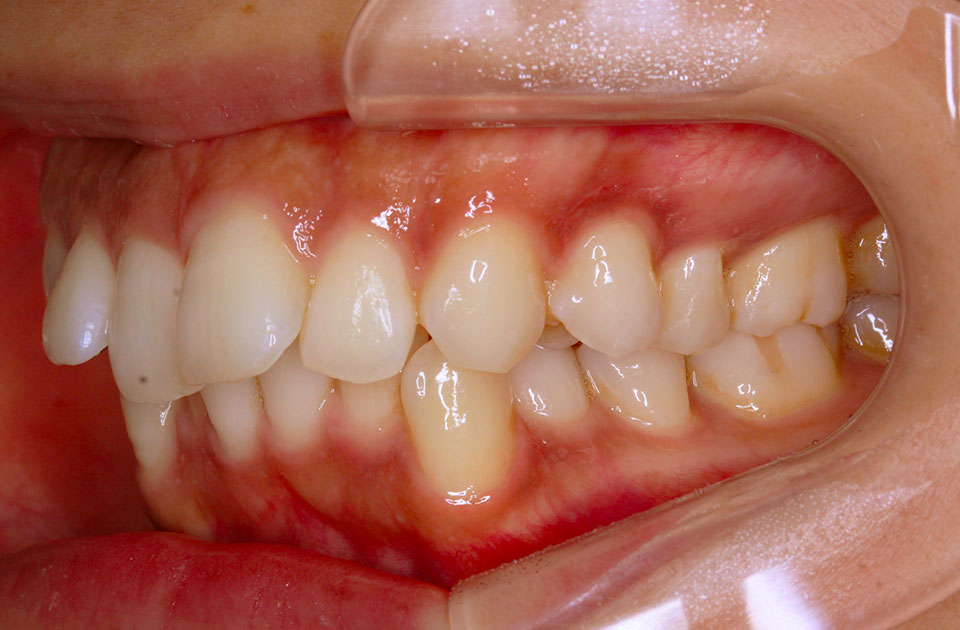

矯正前 右側

矯正後 右側